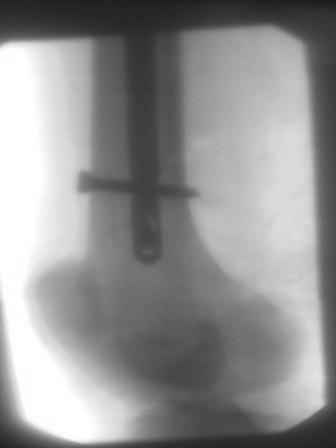

Уважаемый Абдурашид! Штифт у Вас по-видимому MetaDiaFix-F ЦИТОвский? Если так, то по снимку проксимального конца бедра видно, что в динамическом отверстии винт проведен у дистального края.Разрешите мои сомнения. Если это так,то это статический вариант. Запаса на динамизацию в дистальном овальном отверстии не хватит. Я бы оставил как есть. Бедро как правило хорошо срастается. Если будут проблемы - лучше проксимально переблокировать в динамический вариант после появления признаков Rg мозоли. Удачи! С уважением Станислав Дмитриев.

Уважаемый Станислав, штифты действительно ЦИТОвские- ВНПБ (для высоких и низких переломов бедра), Вы правильно заметили , что в проксимальном овальном винт проведен статистическим варианте, а в дистальном у середины овального отверстия, что запаса на динамизацию не хватить., и мне понравился Ваша идея проксимально переблокировать в динамический вариант! так как можно и без ЭОПа и при помощи кондуктора.